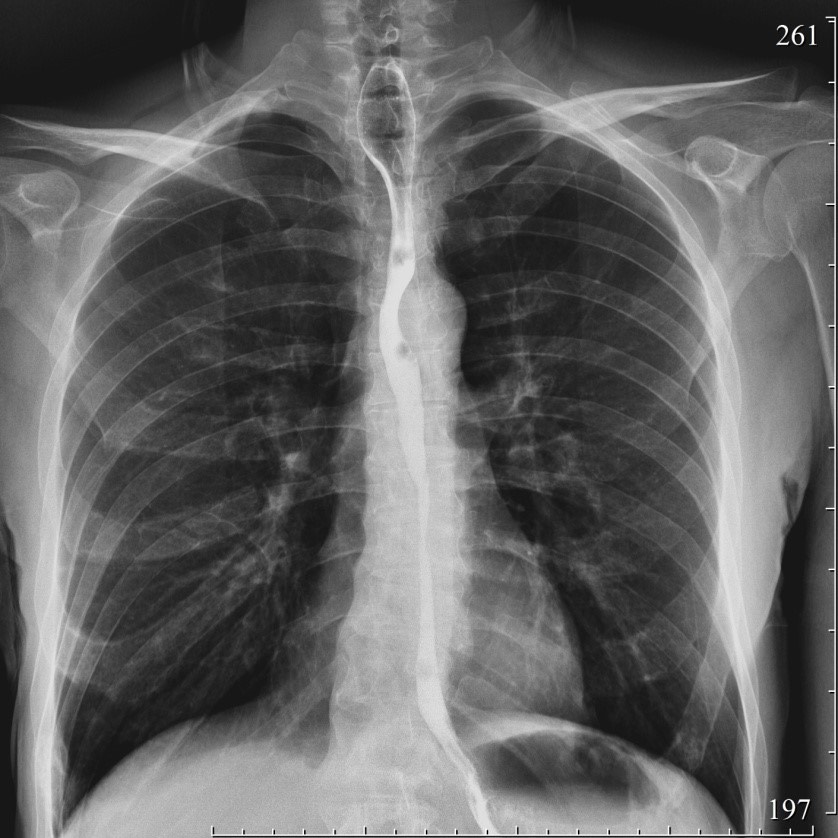

2178. При проведении контрастной рентгеноскопии пищевода с бариевой взвесью определяется